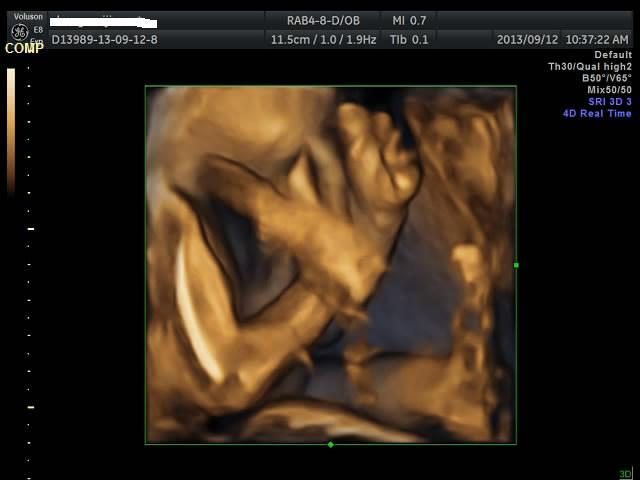

有没有能够帮我看看是千金还是帅哥的朋友?只是好奇是应该准备蓝色衣服还是应该买粉色衣服呢? 点击展开 匿名用户 2013-09-12 20:44 为您推荐: 其他回答 吓死我了... 匿名用户 2013-09-12 20:57 看不出来啊,买米黄色的吧 不论男女,都很好看 匿名用户 2013-09-12 20:57 帅哥的朋友吧,最好选粉红色的 匿名用户 2013-09-12 20:53 要怎么看才好 匿名用户 2013-09-12 20:48 千金,买粉红的 匿名用户 2013-09-12 20:47 相关问题 谁帮我看看是千金还是帅哥! 来看看我家24天的小帅哥,穿粉色衣服么么哒 张凡帅吗?很好奇听说是个帅哥,求解!!!!!!!